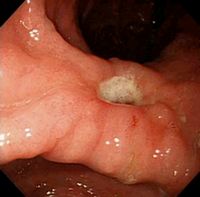

导致十二指肠溃疡的原因 十二指肠溃疡是肠胃病中一种常见的病。它被认为是一种多因素导致的疾病,甚至被认为是一种终身疾病。导致十二指肠溃疡的原因有很多,那么下面我们来听听徐浦中医医院医生为我们分析分析。

3、幽门螺杆菌感染:幽门螺杆菌(helicobacter pylori,Hp)感染和消化性溃疡的发病密切相关。根除Hp 治疗能显著降低溃疡的复发率。Hp 感染是十二指肠溃疡的主要病因,是引起消化性溃疡的重要因素。

4、精神紧张、生活起居:饮食不规律、食物不洁以及神经功能失调等原因可导致胃、十二指肠抵抗力降低,加之胃所分泌的胃酸及消化酶过多,侵蚀了胃、十二指肠的表面,造成溃疡。溃疡的疼痛,是胃酸对破溃的粘膜表面发生刺激作用所造成的。